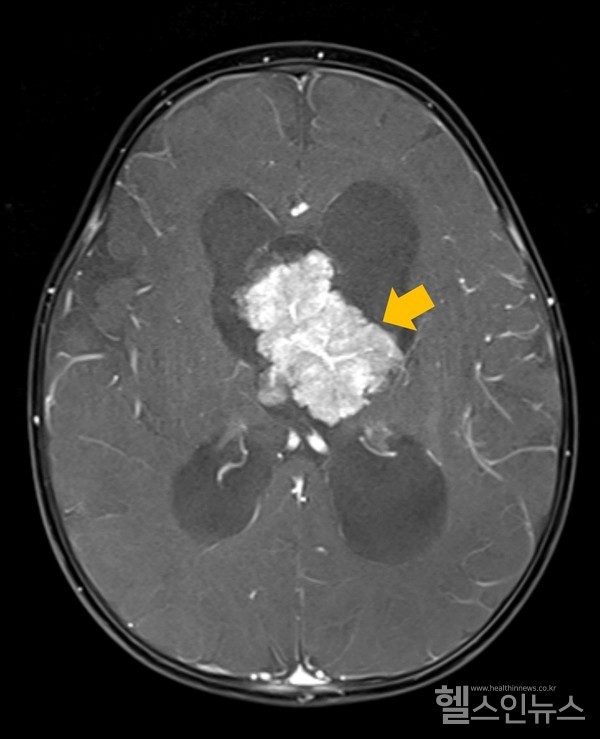

맥락얼기종양은 전체 소아 뇌종양 환자의 2~6%를 차지하며, 주로 5세 미만의 소아에서 진단된다. 조직학적 특성에 따라 ▲맥락얼기유두종(양성 종양, 수술적 제거 후 좋은 예후) ▲비정형 맥락얼기유두종(중간 정도의 예후) ▲맥락얼기암종(악성 종양, 빠른 진행과 재발 가능성 높음)으로 분류된다.

특히 연수막* 전이(암이 다른 조직으로 퍼져나가는 것)를 동반한 맥락얼기암종 환자에서 종양 전이 및 진행과 관련된 유전자들이 과발현되는 것이 확인됐다. 이는 맥락얼기암종의 예후를 결정하는 주요 인자인 연수막 전이에서 유전자 발현이 원발 종양과 달라진다는 것을 시사한다.